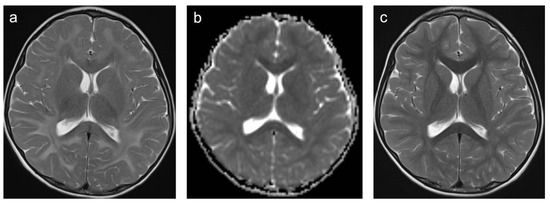

There were only two patients in Group 9. One patient was diagnosed with an isovaleric acidemia and one with a methionine adenosyltransferase I/III deficiency. A representative case is shown in Figure 9. In total, 50% of patients were female and the mean age was 2.2 years (min 1.4 years; max 2.9 years). One patient was examined with contrast-enhanced MRI. None of the examinations showed enhancing lesions. WMSAs in this group of patients were localized supratentorial only. All patients had multifocal WMSAs.

Figure 9. Representative case “Inborn errors of metabolism”: methionine adenosyltransferase I/III deficiency. T2W (a,c) sequences and ADC map (b). Three-year-old boy diagnosed with a methionine adenosyltransferase I/III deficiency. MRI shows T2W signal hyperintensities in subcortical and deep white matter with relative sparing of corticospinal tracts, corpus callosum and optic radiations (a). ADC map demonstrates decreased ADC value of the lesion (b). Normalization of established WMSAs within two years on a strict methionine-restricted diet (c).